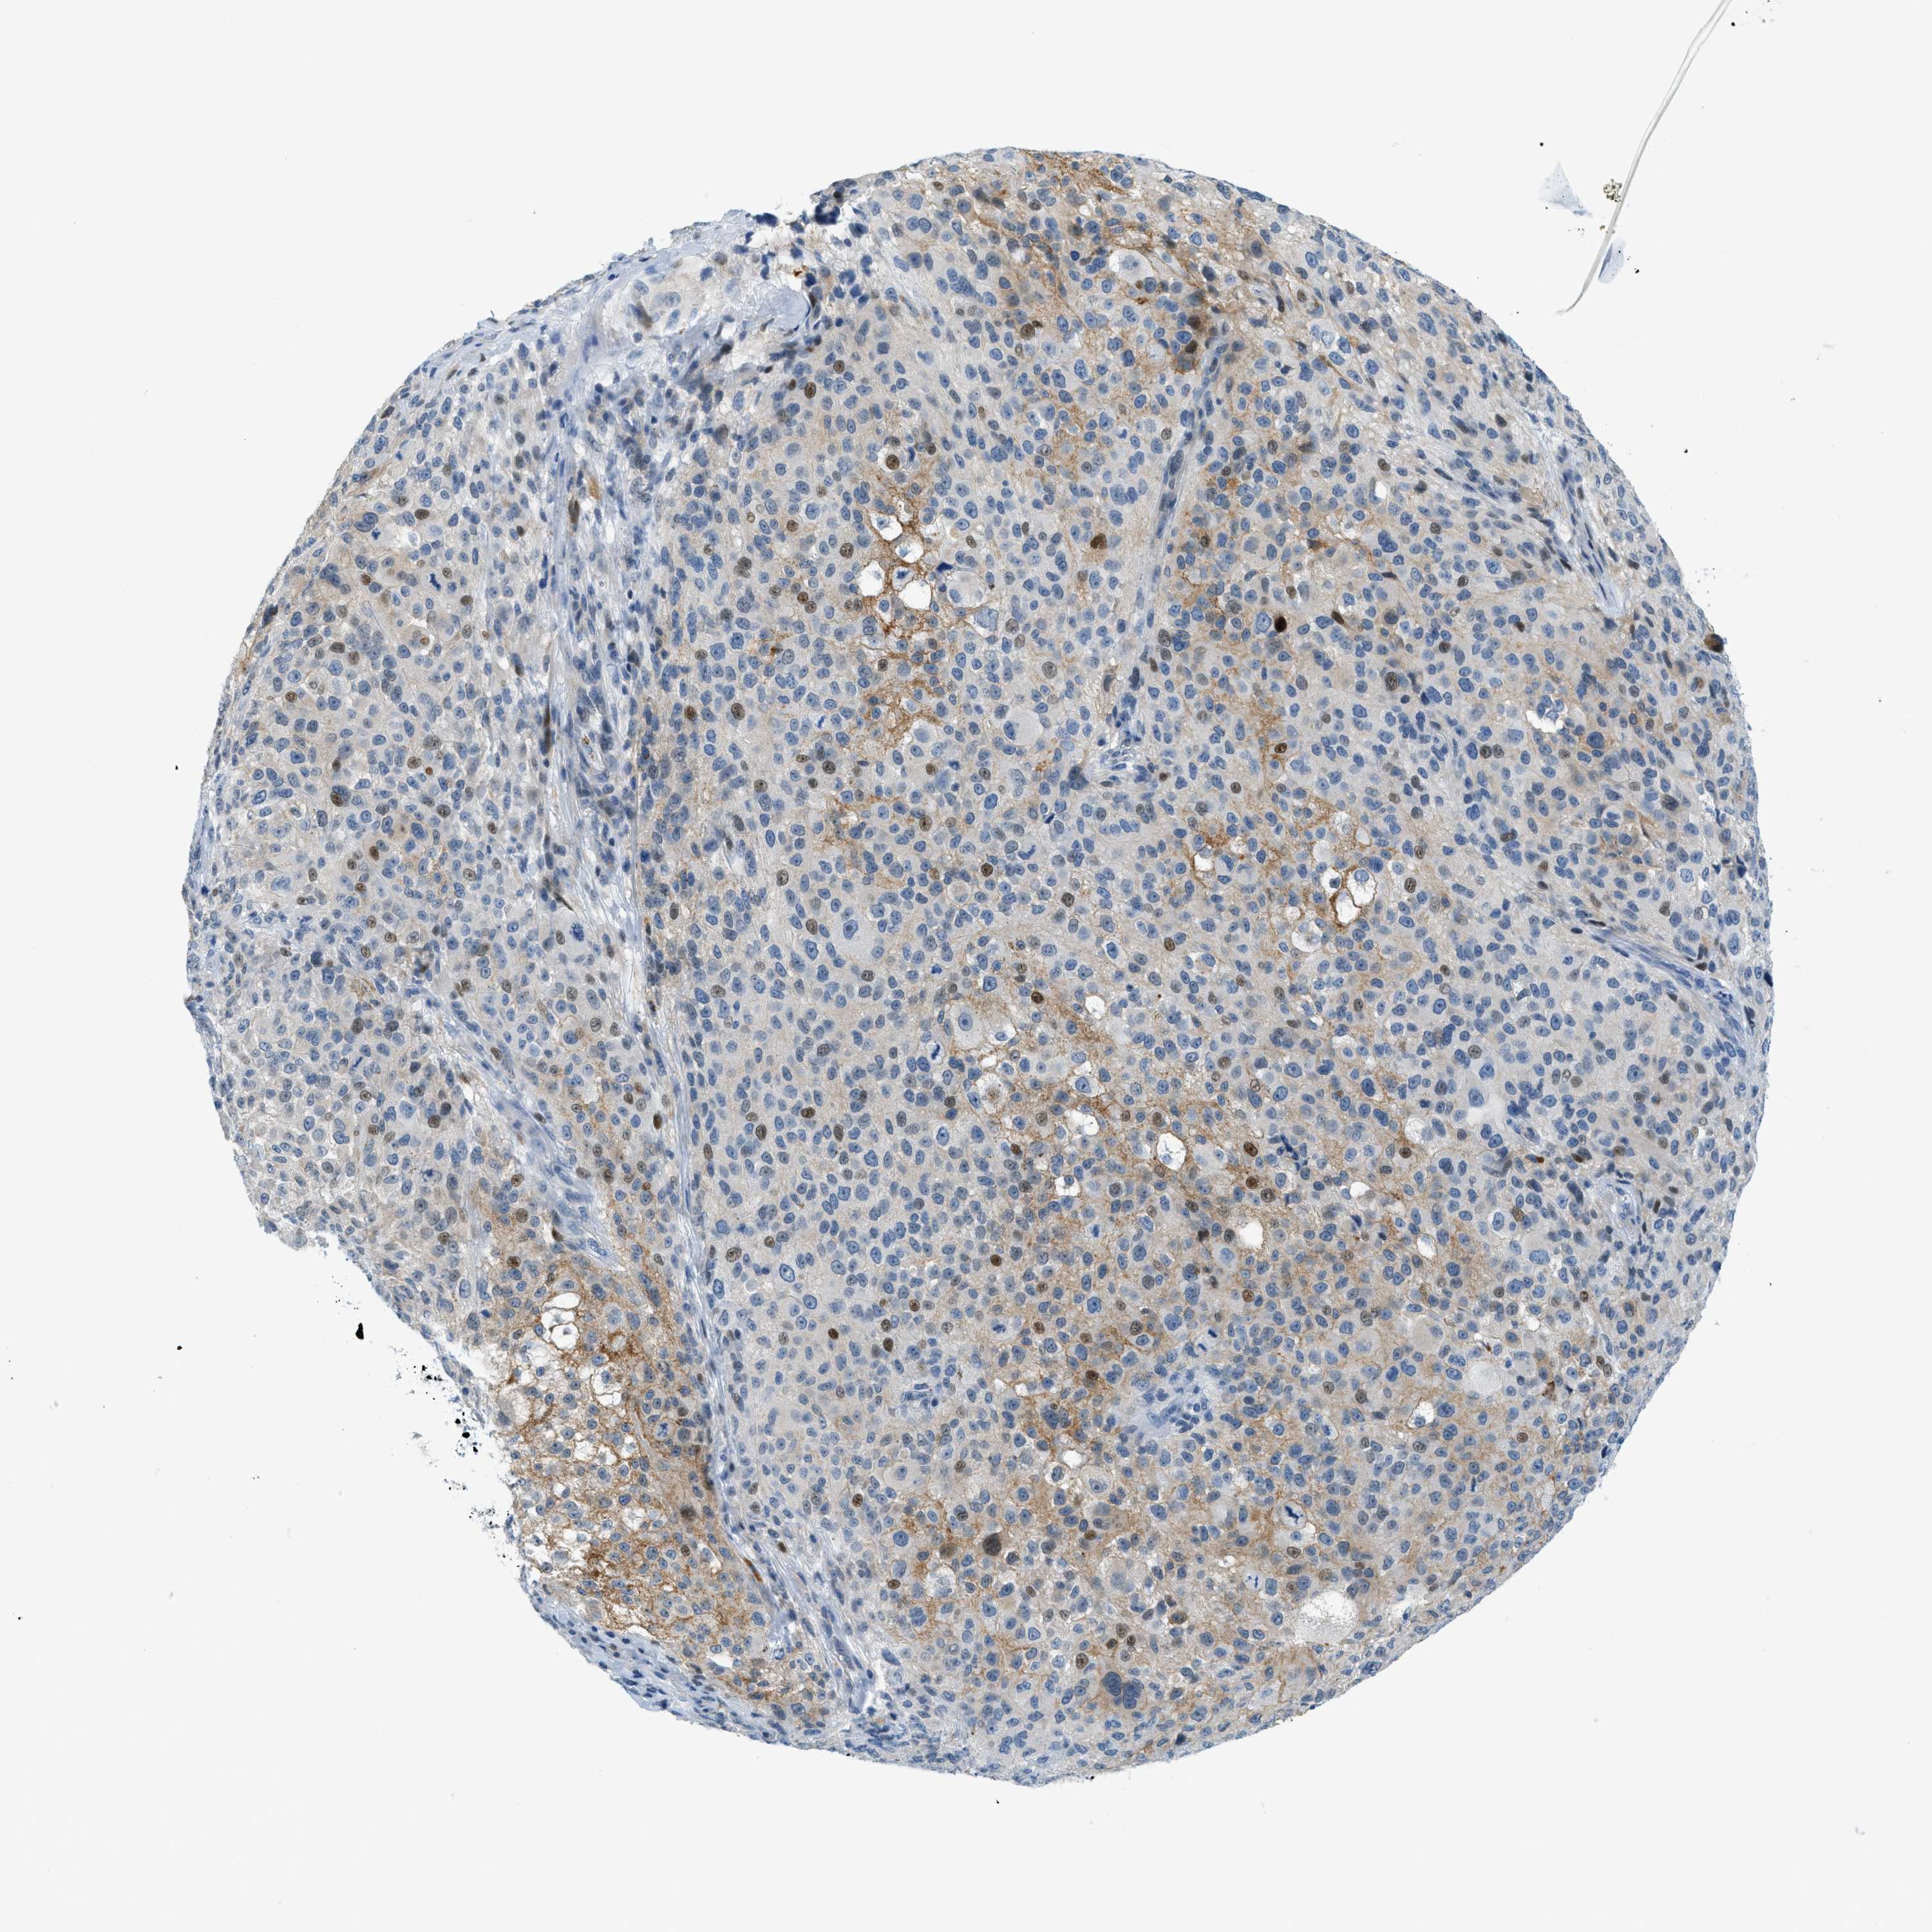

MELANOMA - Protein expressioni

A mouse-over function shows sample information and annotation data. Click on an image to view it in a full screen mode. Samples can be filtered based on level of antibody staining by selecting one or several of the following categories: high, medium, low and not detected. The assay and annotation is described here.

Note that samples used for immunohistochemistry by the Human Protein Atlas do not correspond to samples in the TCGA dataset.

Antibody stainingi

Antibody staining in the annotated cell types in the current human tissue is reported as not detected, low, medium, or high, based on conventional immunohistochemistry profiling in selected tissues. This score is based on the combination of the staining intensity and fraction of stained cells.

Each image is clickable and will lead to virtual microscopy that enables deeper exploration of all samples and also displays staining intensity scores, fraction scores and subcellular localization as well as patient and tissue information for each sample.

Antibody HPA017661

Staining

High

Medium

Low

Not detected

Intensity

Strong

Moderate

Weak

Negative

Quantity

>75%

75%-25%

<25%

None

Location

Nuclear

Cytoplasmic/membranous

Cytoplasmic/membranous,nuclear

Malignant melanoma, NOS

Malignant melanoma, Metastatic site